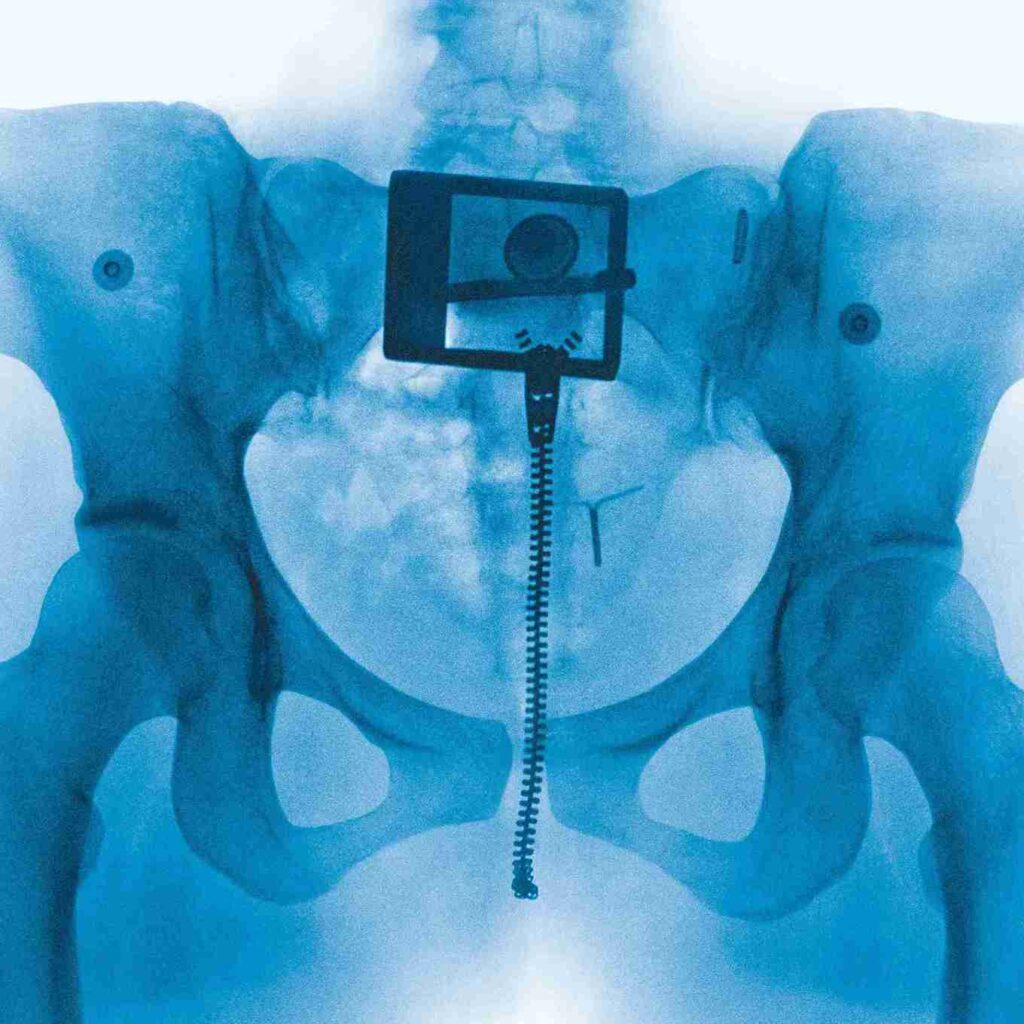

Virgin เป็นผลงานอัลบั้มที่ Lorde ได้ร่วมโปรดิวซ์กับโปรดิวเซอร์คู่บุญ Jim-E Stack ออกมาเป็น 11 เพลงที่เธอได้ทดลองทำดนตรีในรูปแบบใหม่ ๆ แต่ยังคงไว้ซึ่งลายเซ็นของเธอเอาไว้ได้เป็นอย่างดี ไม่ว่าจะเป็นเพลงในแนว summer song สมชื่อ Lorde Summer ที่แฟน ๆ เรียกกัน และเนื้อเพลงที่คมคาย สื่อสารถึงผู้ฟังได้อย่างตรงไปตรงมา เป็นอัลบั้มใหม่ชุดที่ 4 ที่สมการรอคอยกว่า 4 ปีอย่างแท้จริง